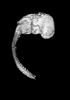

Carnegie Stage 23 (56 post-ovulatory days)

Most embryos at stage 23 are approximately 56-57 postovulatory days old and measure 23-32 mm in length. Distinguishing criteria for this stage include fusion of the eyelids at the medial and lateral margins, clear distinction of the subdivisions of the upper and lower limbs, the forearms appear at or above the level of the shoulders, the superficial vascular plexus of the head is very close to the vertex, and the external genitalia are well developed but not always sufficiently to distinguish the embryo's sex.

(NOTE: These specimens are late stage 23.)